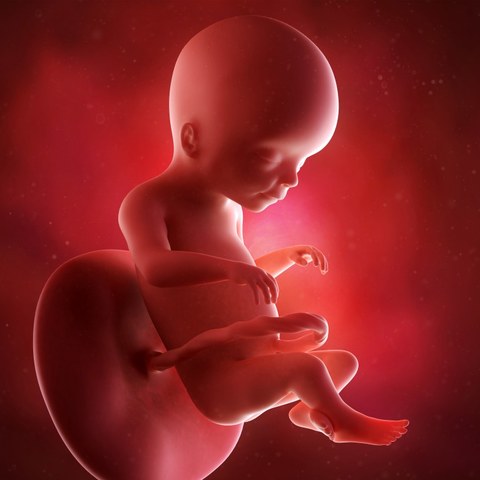

Semana 14

Las orejas del feto se encuentran implantadas a ambos lados de la cabeza y también los ojos se han acercado; tanto que ya se distingue el puente de la nariz.

- Su cabeza sigue siendo mucho más grande en proporción con su cuerpo.

- Su hígado es aún muy grande, porque tiene que fabricar células sanguíneas

- Su piel sigue siendo tan sumamente fina que a través de ella se pueden ver algunos de los órganos internos y los vasos sanguíneos.